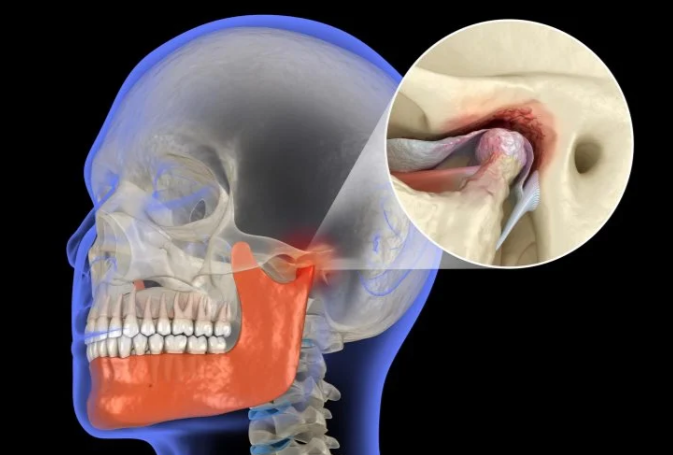

Nyja temporomandibulare (TMJ) është lidhja që bashkon nofullën e poshtme me kafkën. Ajo mbështetet në kërc dhe një disk mbrojtës për të përballuar presionin e vazhdueshëm gjatë lëvizjes. Kur ky ind fillon të dëmtohet, procesi shpesh është i pakthyeshëm, pasi kërcet kanë aftësi të kufizuar për t’u rigjeneruar.

Studiuesit nga Boston University analizuan rolin e enzimës LOXL2 duke përdorur modele eksperimentale me minj të modifikuar gjenetikisht dhe mostra kërcore nga dhitë, të cilat kanë strukturë të ngjashme me nyjën e nofullës së njeriut. Ata zbuluan se mungesa e LOXL2 aktivizon procese inflamatore që dëmtojnë qelizat e kërcit (kondrocitet) dhe përshpejtojnë degradimin e indit.